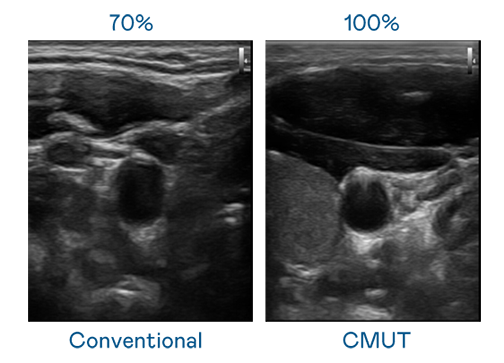

CMUT 技术是一种用电容式微机电元件来产生超音波讯号的技术。与传统 PZT 压电式技术相比,CMUT 频宽增加 30%,更宽频的超音波讯号让影像解析度大幅提升,是实现高影像品质医疗超音波扫描、促进精准医疗发展的关键技术。

超音波影像的解析度高低,首先取决于探头能发出的讯号频宽。bifa必发 CMUT 可提供高清晰的超音波讯号,提供高频宽、高灵敏度、影像纹理细节更高的超音波影像,协助医护人员缩短影像判读时间及利用精准的医疗影像进行诊断。